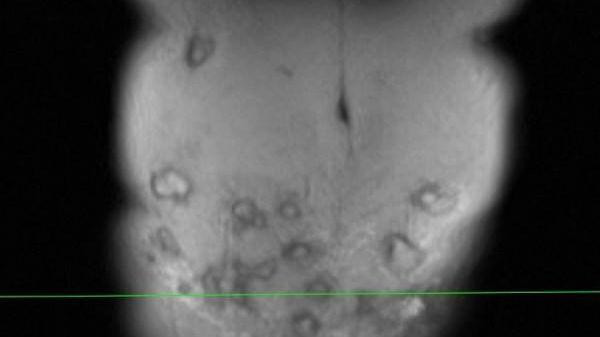

Bụng bệnh nhân có nhiều khối áp xe.

Bác sĩ Minh cho biết, vùng thành bụng bệnh nhân bị viêm phản ứng nặng, vùng da ngoài thành bụng đỏ, nổi gồ ghề, sờ bên dưới có hàng chục khối tổ chức vón cục, áp xe....

“Bệnh nhân này có thể tạo hình lại thành bụng, đồng thời giải quyết được 20 khối áp xe lớn nhỏ. Tuy nhiên, do vùng tiêm rộng nên việc lấy hết ổ áp xe này không dễ dàng. Với những khối áp xe tiêm ở vị trí cao như hạ sườn thì quá trình xử lý sẽ để lại sẹo, gây mất thẩm mỹ”, bác sĩ Minh chia sẻ.